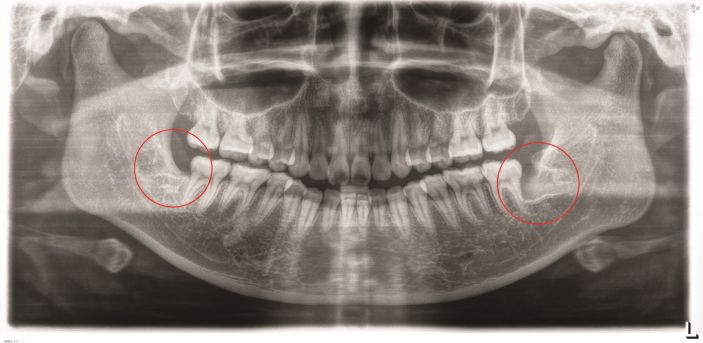

△阻生智牙。

低位埋伏阻生智齒是臨床上常見的口腔疾病,易導緻颌骨囊腫、骨髓炎和冠周炎等,影響患者的正常生活。對這種沒有咀嚼功能,且反複引發口腔問題的智牙是需要拔除的。但此類智牙的位置較深,骨阻力較大,周圍結構複雜,操作空間有限,要拔除是非常有挑戰性的。

△智牙拔除前。